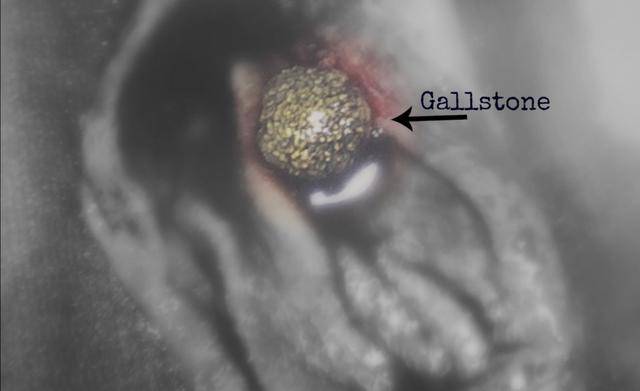

结石变癌不是吓唬人!这2个吃饭习惯正在掏空你的胆,现在改还来得及“医生,我是不是又长结石了?这次比上次还疼,连腰都直不起来了!”在泌尿外科门诊,王先生捂着右腰,一脸痛苦。他去年刚做过一次肾结石手术... 易形成结石。研究发现,不吃早餐者患胆囊结石风险比规律饮食者高2.3倍。 看到这里,你可能会问,那我们应该怎么预防胆囊结石呢?首先,要养成...